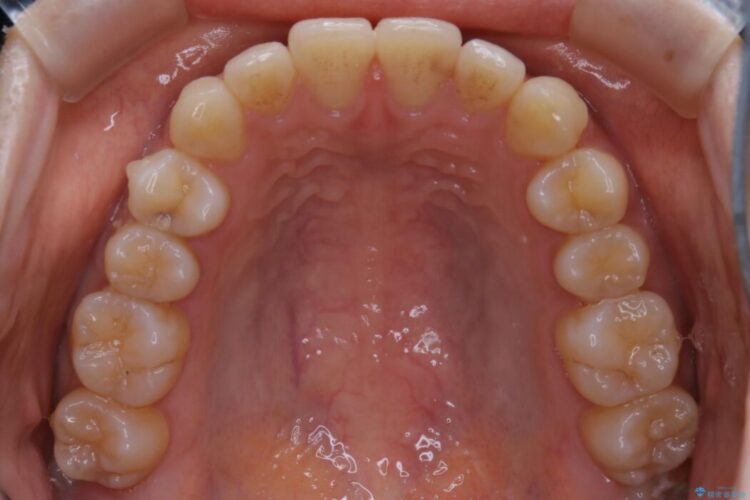

- 治療期間:6ヶ月

- 矯正装置:インビザライン ライトパッケージ

通常の全体矯正と比べピンポイントの部分矯正となると、動かす歯が少なくなるため治療期間が格段に短くなり、費用が抑えられることがメリットとして挙げられます。